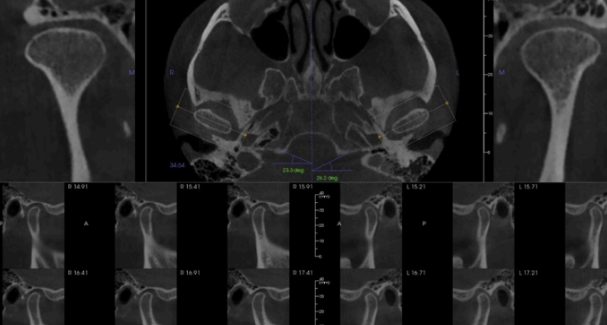

What CBCT view is presented, and what type of contrast is shown on the right ?

sagittal; high